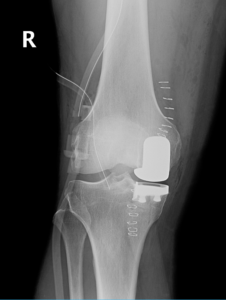

During the surgery, a small incision is made over the knee to expose the knee joint. Your surgeon will remove only the damaged part of the meniscus and place the implant into the bone by slightly shaping the shin bone and the thigh bone. The plastic component is placed into the new prepared area and is secured with bone cement. Now the damaged part of the femur or thigh bone is removed to accommodate the new metal component which is fixed in place using bone cement. Once the femoral and tibial components are fixed in proper place the knee is taken through a range of movements. The muscles and tendons are then repaired and the incision is closed.

Unicompartmental knee replacement, also called a partial knee replacement is surgery to treat arthritis which is limited to one of the knee compartments. During the surgery, only the damaged compartment of the knee is removed and replaced with metal and plastic, leaving the remaining healthy cartilage and bone.